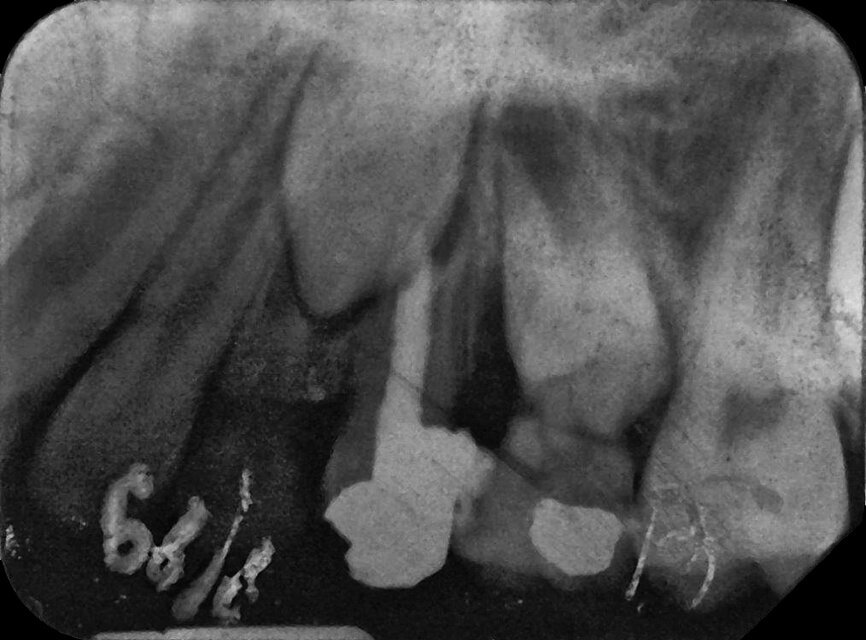

Case 3: Female (born 8 August 1988): Tooth 11

Fig. 5a: 4 September 1995 ante RCF

(non-vital).

Fig. 5b: 4 September 1995 post RCF

Fig. 5c: 22 April 2002 status.